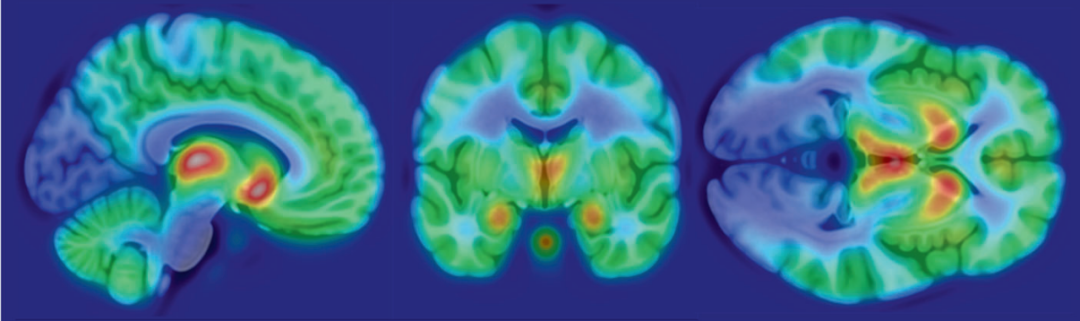

阿片受体分布图(PET图)

来源:Neuropsychopharmacology论文

图尔库大学的Lauri Nummenmaa教授说:我们发现受试者的抑郁症和焦虑症症状越严重,大脑中的阿片受体就越少。受体减少会导致内源性阿片样物质利用率降低,通过PET显示降低的脑区域主要集中在杏仁核,海马,腹侧纹状体,眶额和扣带回皮质中,这些脑区域与情绪管理区域高度重合。